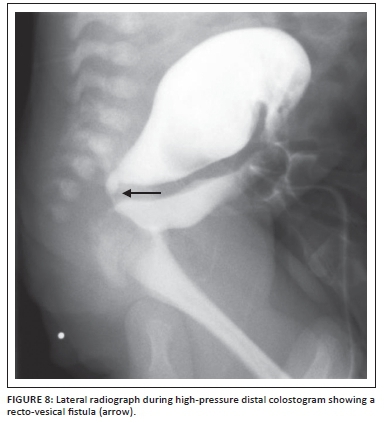

A Foley catheter is then inserted into the distal fistula and 3 ml of saline is injected into the balloon. Gentle traction is applied to the catheter to create a seal so that adequate pressure can be applied when injecting the contrast. A radio-opaque marker is placed where the anus should be. Contrast medium (water soluble) is injected via the Foley catheter with a 50 ml catheter tip syringe into the rectum under gentle but increasing pressure until the distal rectum and fistula are identified. The AP view is pivotal to see how much distal bowel is present, and the lateral view then defines the distal rectal anatomy as it relates to the urinary tract. Fluoroscopy with spot filming with the child in AP and then lateral position is performed. Sufficient pressure must be applied to distend the distal rectum adequately and identify the fistula.

It is worth noting that too much pressure may cause bowel perforation or decrease the actual distance from distal rectum to skin, giving the impression of a falsely low pouch. However, too little pressure will give the false impression of a high rectum with no fistula; this will show up as a flattening of the distal rectum at the pubococcygeal line, and means more pressure is required for an accurate study. In most cases where there is not a fistula to the bladder, the study will be considered completed once contrast has reached the level below the pubococcygeal line, indicating that enough pressure has been applied. The sacrum, coccyx, perineum and bladder must all be visible during fluoroscopy. If a fistula is identified, it is suggested to continue injecting the contrast until the bladder fills and the baby spontaneously voids. If this is the case, valuable information regarding the urinary tract can be obtained. It is in essence a modified MCUG14 (Figures 8- 10).

The information that the surgeon would like to know is the precise location of the fistula in relation to the urinary tract, the length of bowel available for the pullthrough procedure, and the relationship between the sacrum, coccyx and rectum. All this information is vital to plan the type of operation required (PSARP, laparotomy or laparoscopy).9 The usual surgical approach for a bulbar or low prostatic fistula would be PSARP. For a vesical or high prostatic fistula, the approach would normally be laparotomy or laparoscopy for ligating the fistula and mobilising the bowel, then a limited PSARP incision to bring it down to the cutaneous junction in the centre of the muscle complex. It must be emphasised, however, that not every patient fits this formula, and one may find a low prostatic fistula that has a long fistula with a rectal stump that is high. Such a patient would do best with a laparotomy/laparoscopy first, followed by a limited PSARP (Figure 11).